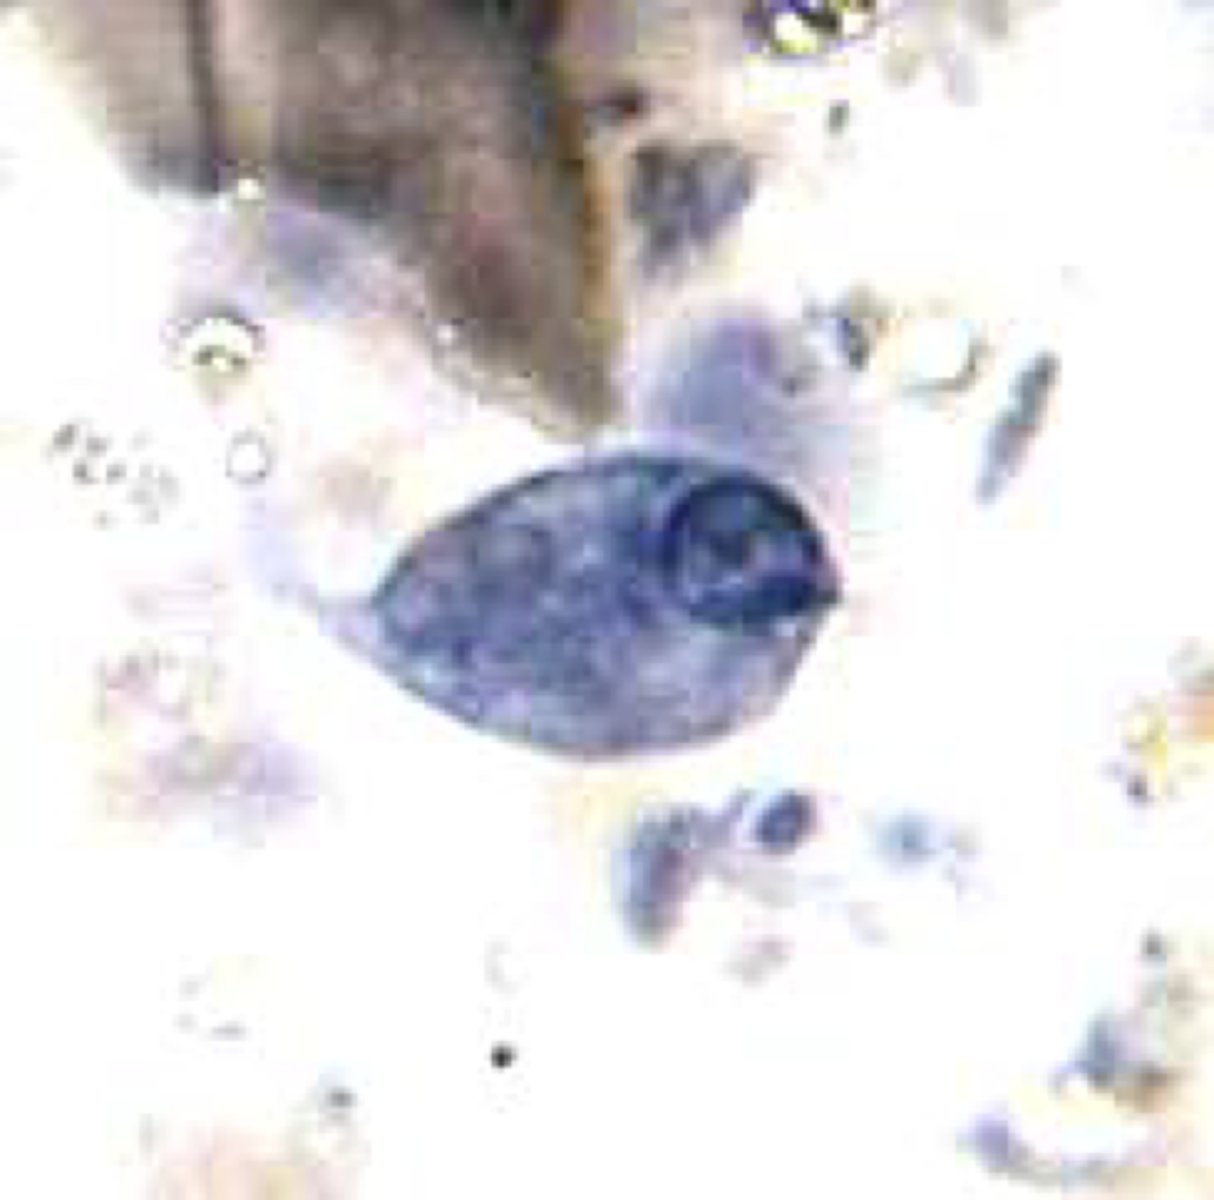

Leishmania donovani - Promastigote

elongated, mobile, and extracellular form of the Leishmania parasite found in the sand fly vector's midgut, characterized by a flagellum for motility, a nucleus, and a kinetoplast

<p><span>elongated, mobile, and extracellular form of the Leishmania parasite found in the sand fly vector's midgut, characterized by a flagellum for motility, a nucleus, and a kinetoplast</span></p>